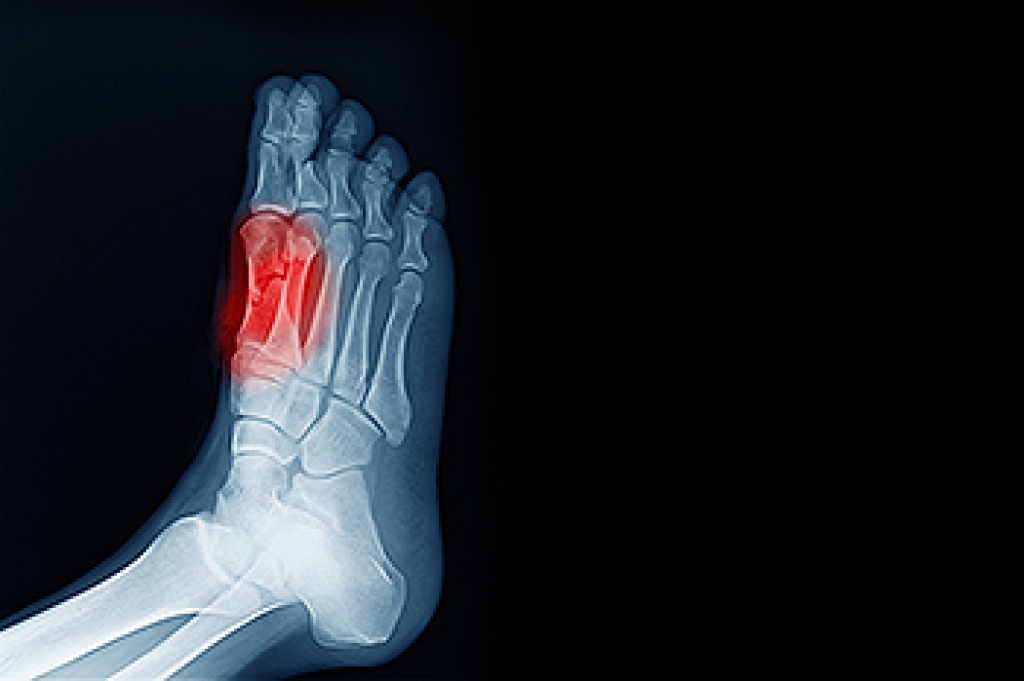

In many cases the cause of toe pain is obvious, but in others, a podiatrist may want to use more advanced methods to determine the problem. These can range from simple visual inspections and sensation tests to X-rays and MRI scans. Prior medical history, family medical history, and any recent physical traumatic events will all be taken into consideration for a proper diagnosis.

Treatments for toe pain and injuries vary and may include shoe inserts, padding, taping, medicines, injections, and in some cases, surgery. If you believe that you have broken a toe, please see a podiatrist as soon as possible.